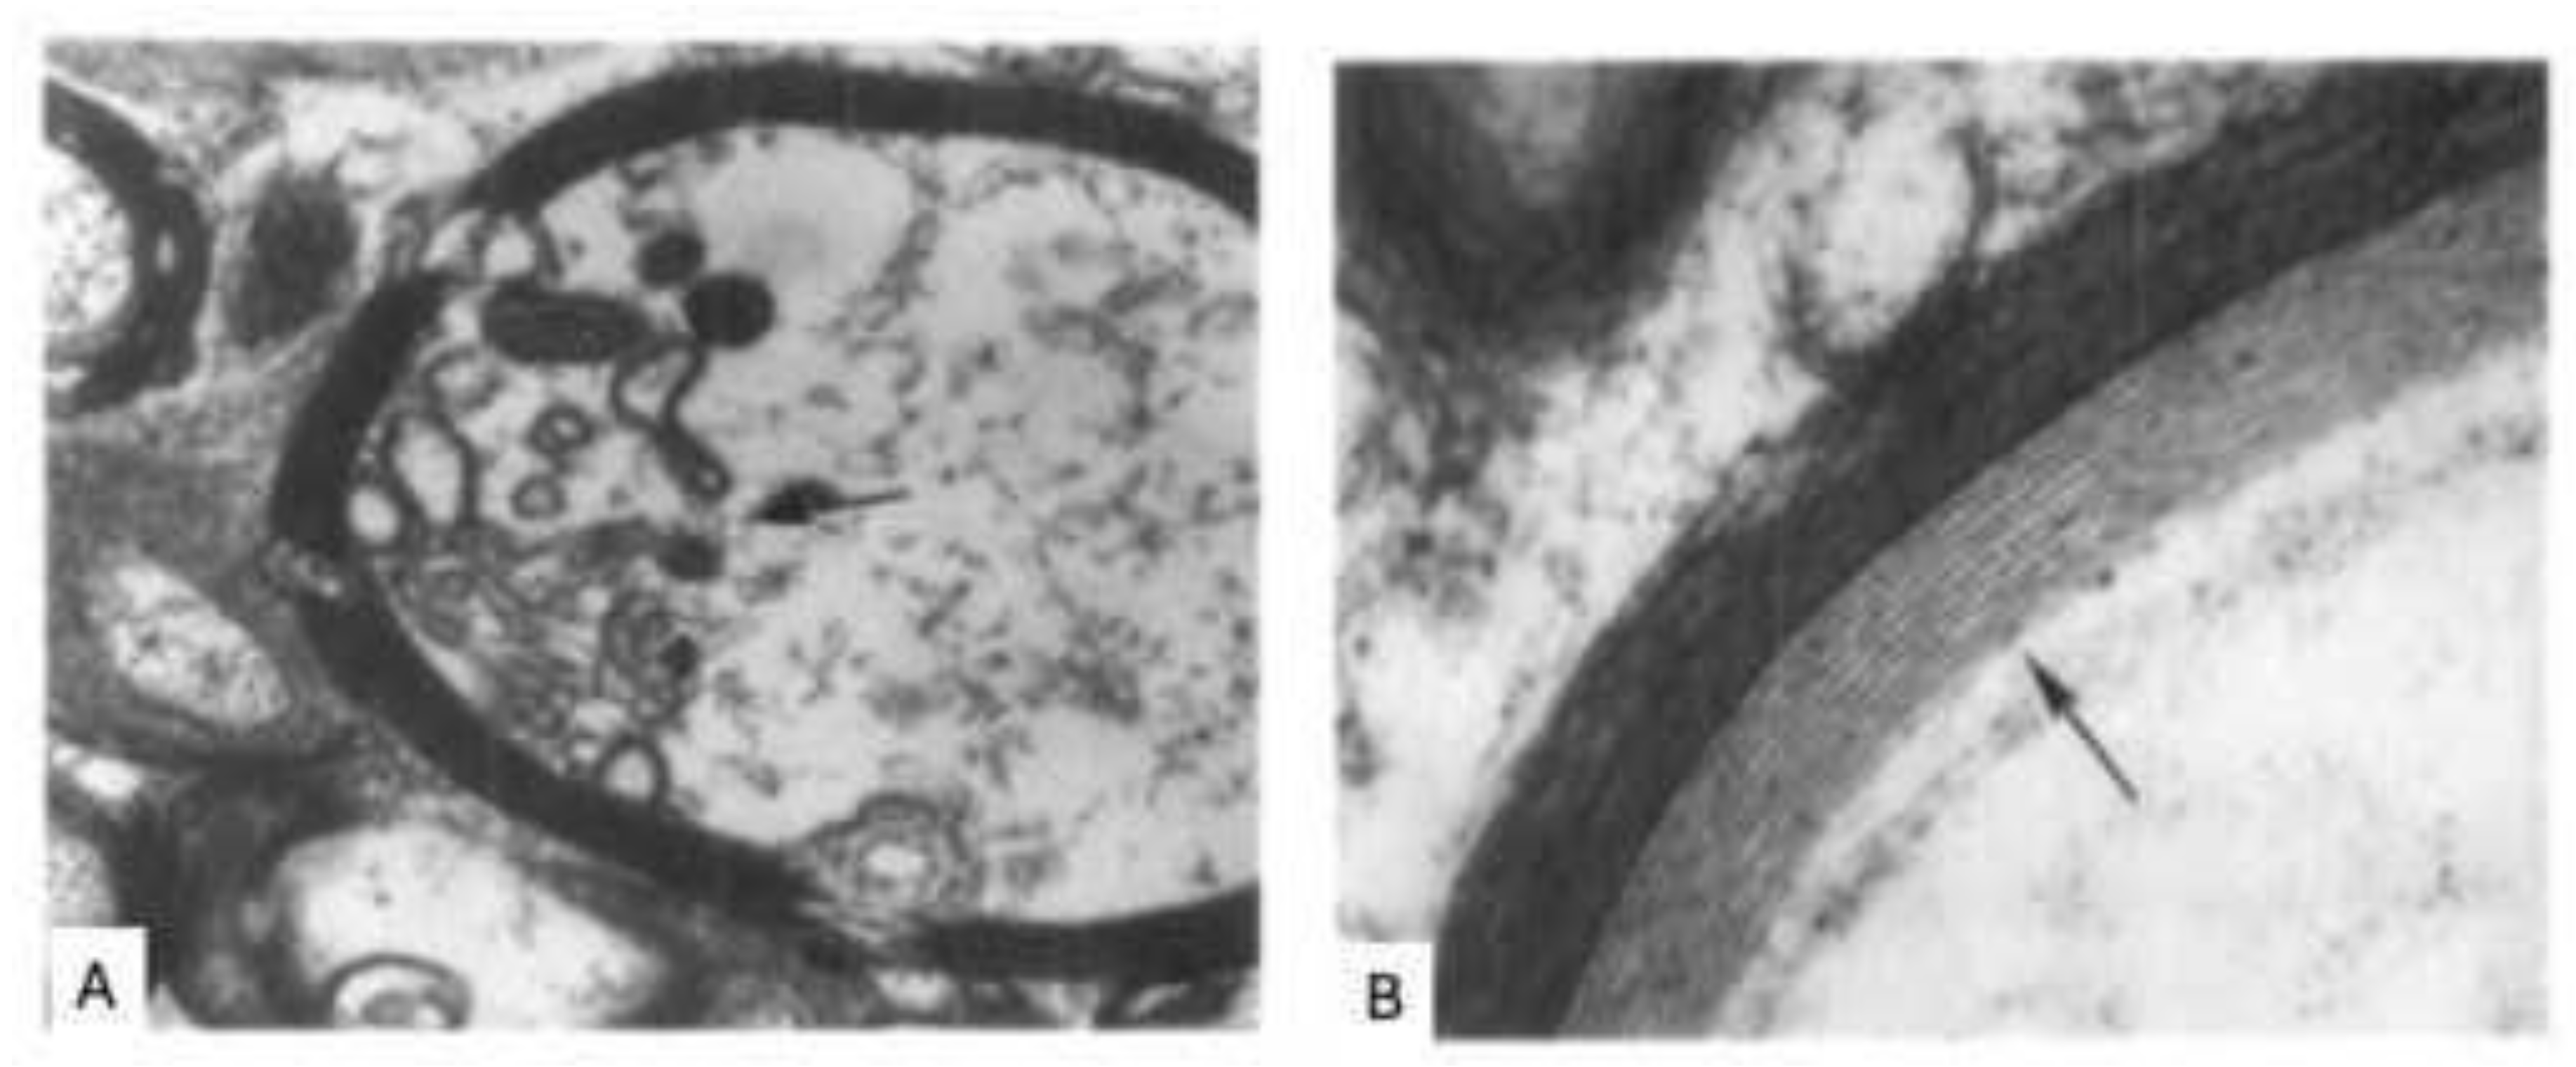

- Rodriguez, M.; Scheithauer, B. Ultrastructure of multiple sclerosis. Ultrastruct Pathol 1994, 18(1-2), 3–13. [Google Scholar] [CrossRef]